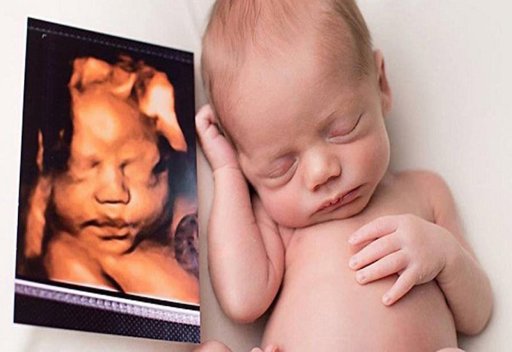

Tất tần tật về siêu âm màu thai nhi mẹ bầu cần ghi nhớ

Trong quá trình mang thai mẹ bầu rất cần được nhìn thấy hình ảnh của con trong bụng để biết được tình trạng và sức khoẻ của con. Đó chính là lý do để phương pháp siêu âm thai nhi ra đời. Khác với siêu âm 2D truyền thống, siêu âm màu thai nhi được cho là cải tiến hơn vì có thể giúp mẹ nhìn thấy co...

Cẩm nang tư vấn về siêu âm màu dành cho phụ nữ mang thai

Việc thực hiện siêu âm trong thời gian thai kỳ chính là sợi dây kết nối tốt nhất giữa mẹ và bé, đặc biệt là các kỹ thuật hiện đại như siêu âm màu. Bài viết hôm nay chúng tôi sẽ tư vấn cho các bạn những vấn đề liên quan đến siêu âm thai nhi màu hiện nay tại hệ thống Bệnh viện Đa khoa MEDLATEC, nhằ...